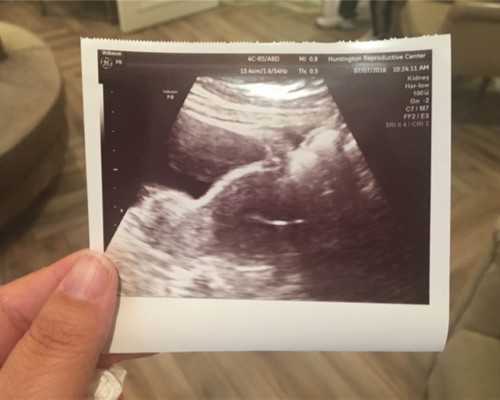

其次就是孕妈妈们如果要是前去香港验血检测自己宝宝性别的话,那么一定要在出发之前自己确认一下肚子里的胎儿的胚芽生长情况,香港验血检测宝宝的性别是要求宝宝胚芽长度必需满足长到10mm或者以上的距离才可以进行,因为只有满足这个基本条件之后,孕妈妈们的血液当中所含有的宝宝DNA成分浓度才符合香港验血检测鉴定的最低标准,所以孕妈妈们一定要检查确认,一般在怀孕满够七周的时候就会符合这个条件,孕妈妈们可以在孕检的时候通过B超结果进行检查。

香港验血中为什么孕期要用B超确定?许多准妈妈都知道香港验血鉴定胎儿宝宝性别,其中也有不少大陆的准妈妈们做过香港验血。香港七周验血鉴定胎儿宝宝性别的鉴定中需要用到孕妈的血,而这个血液是有时间限制的,要求是妊娠期满七周或者以上才可以,所以去过香港医院的准妈妈的都会被问孕期有几周了。这里的孕期有几周是严格按照B超检查的为准,这是香港验血鉴定胎儿宝宝性别的首要条件。只有满足妊娠期满七周才可能够进行抽取孕妈手臂少量静脉血,在进行化验时也才能保证99.8%的准确率。那么为什么进行香港验血时需要以B超的周期为准呢?下面请小编在此专家为大家科普一下。通过生物医学知识我们可以知道人体是由细胞组成的,而人类的生长发育就会伴随有新老细胞的交替,即新的细胞产生,老化的细胞脱落。因此胎儿宝宝细胞在生长发育时衰老的脱落的细胞就会通过母体胎盘渗入到孕妈的血液循环系统中,而宝妈的免疫系统系统会破坏胎儿宝宝细胞,从而使DNA遗传物质进入到孕妈的血液当中,此时胎儿宝宝细胞中的DNA遗传物质会不断累积,当在孕妈妊娠期满七周的时候浓度达到最大,一直到分娩前浓度稳定不变。所以这个时候利用技术检测宝宝DNA是最精确的,准确率也是最高的!如果孕妈孕期不满七周会有哪些结果呢?如果孕妈孕期不足香港医院是不允许抽血化验的,其次即使能给你抽血化验那结果也会存在许多偏差,准确率达不到99.8%,还有可能翻车。关于香港验血不仅要满足B超满7周还需要满足以下注意事项才能进行抽血检查!首先孕妈的胚芽长度达到10mm或者以上,也是为了保证孕妈身体健康,排除宫外孕子宫肌瘤等。其次一定保证宝妈没有经历过重大输血和器官移植等重大型手术。最后还需要确保宝妈在6个月内没有经历过流产男孩,并且12个月内没有生过男孩的经历,如果流产的是女孩以及生的是女孩则不影响化验。小编在此温馨提示:想要提前知道胎儿性别的准父母们需要提前1-2天预约,验血前无需空腹,可以正常饮食,避免油腻辛辣刺激过甜的食物即可!孕妈去香港验血鉴定胎儿宝宝性别的时候一定要记得带上B超单,如果没有B超检查单是不给进行抽血化验,这也体现了香港医院的严谨性!